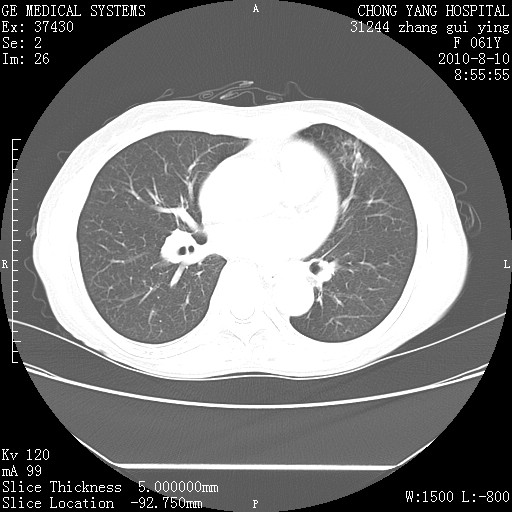

标题: CT28314:F61Y胸部增强,发热咳嗽一周入院,后面的为一周前平 [打印本页]

标题: CT28314:F61Y胸部增强,发热咳嗽一周入院,后面的为一周前平

1、支持考虑右侧中央型肺癌伴右肺中叶节段性不张及下叶支气管黏液痰栓    2、左肺上叶舌段感染。

支持右下肺中央型肺癌并左上肺感染.

我也觉得右肺中叶支气管受累

支持3楼意见,还要考虑:纵隔及肺门淋巴结转移、右侧少量胸腔积液。

确切的说:1:右肺下叶中心型肺癌侵及中叶支气管并中叶不张,纵膈淋巴结转移。2:左肺舌叶炎症。3:右侧胸腔少量积液

块影平扫32hu,动静脉期62-70hu.